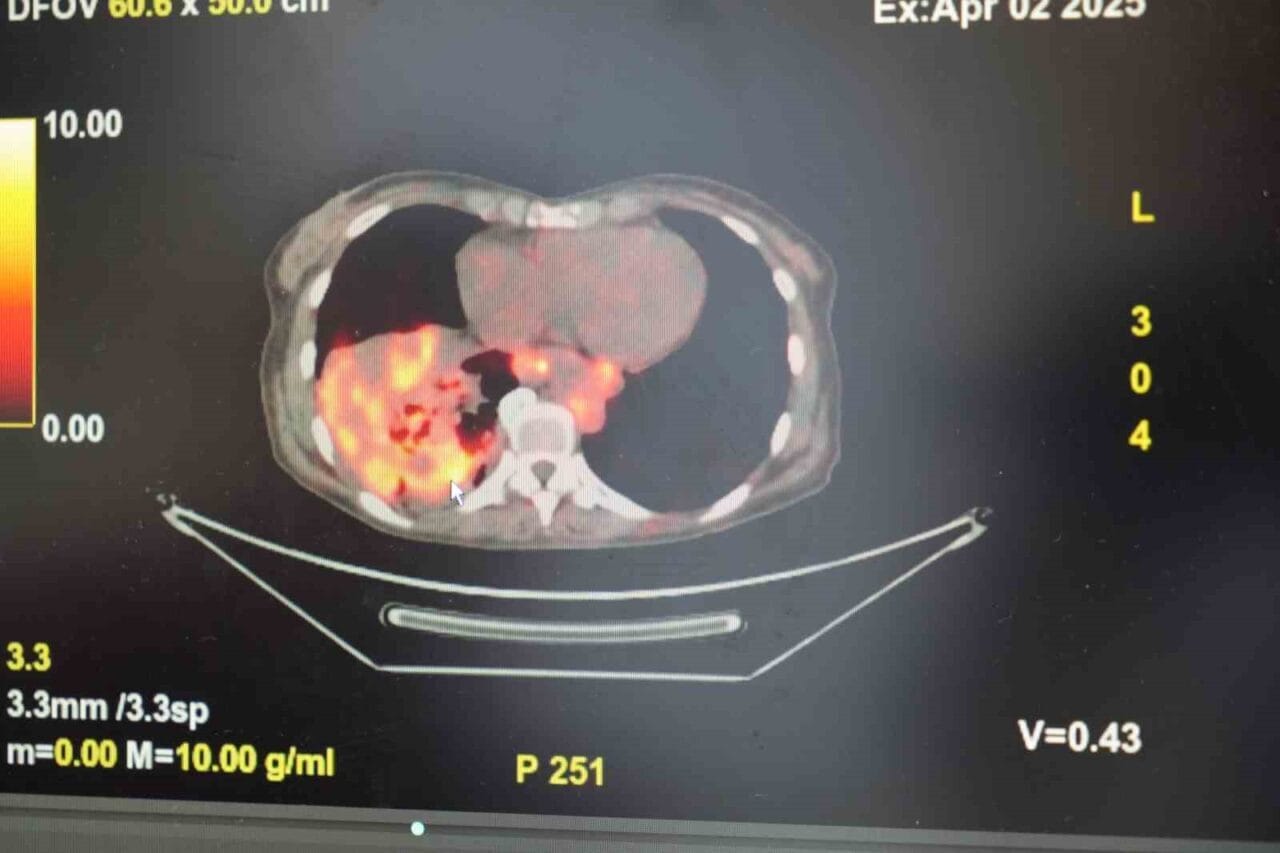

’Sigarasız akciğer kanseri’ vakalarında dikkat çeken artış

Göğüs Hastalıkları Uzmanı Prof. Dr. Şevket Özkaya, son yıllarda sigara kullanmayan bireylerde de akciğer kanseri vakalarının dikkat çeken bir oranda